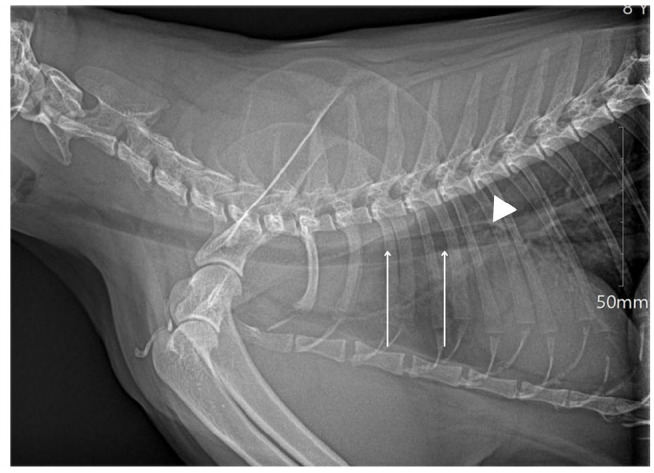

Case series summary: Two cats were referred to a veterinary teaching hospital with a cotton tip applicator (CTA) tracheobronchial foreign body (FB) after induction of anesthesia for an elective dental cleaning. In both cases, a lidocaine-saturated CTA, utilized to desensitize the larynx before endotracheal (ET) intubation, broke when introduced into the oropharynx and was subsequently aspirated into the tracheobronchial tree. Both CTAs were successfully removed bronchoscopically, and the cats survived with no short- or long-term complications noted.

Relevance and novel information: Utilizing a lidocaine-saturated CTA to facilitate ET intubation in cats is not well described, and information on the relative risks and benefits of this specific method for laryngeal desensitization is lacking. This retrospective case series is the first to describe a complication of this technique and successful treatment. These cases highlight the risk inherent to using a CTA to desensitize the feline larynx.